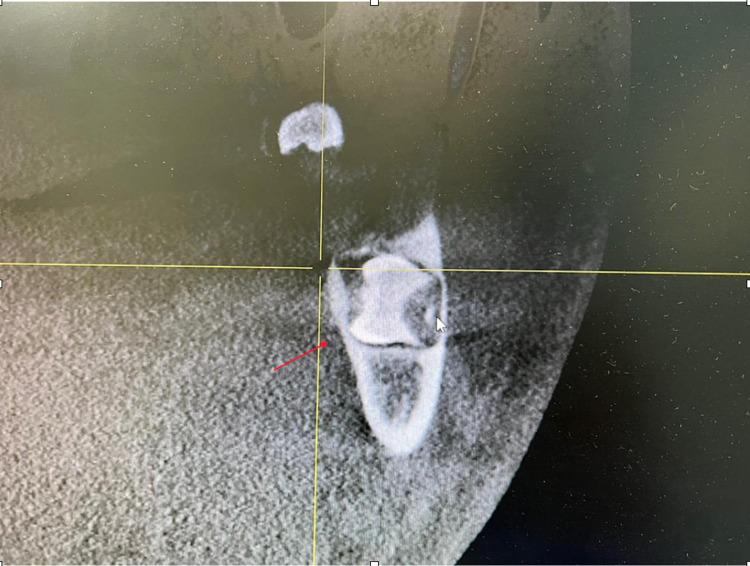

Symmetrical horizontal impacted bilateral mandibular third molar in lingo-buccal direction is a rare type of impacted teeth. When a tooth cannot erupt and fails to achieve a normal function and occlusion during its chronological age of eruption, it is called an impacted tooth. In this paper, a case of a male patient aged 20 years old who had bilateral horizontally impacted lower third molar which was noticed in a routine screening panoramic radiograph and confirmed with cone beam computed tomography (CBCT) imaging and referred to the oral maxillofacial surgical center for surgical removal of the impacted teeth in order to avoid late complications is discussed.

摘要

双侧下颌第三磨牙在舌颊向呈对称性水平阻生是一种罕见的阻生牙类型。当一颗牙齿在其正常萌出年龄时不能萌出且无法实现正常功能和咬合时,就称为阻生牙。本文讨论了一例20岁男性患者,其双侧下颌第三磨牙水平阻生,在常规筛查全景X线片上被发现,并经锥形束计算机断层扫描(CBCT)成像证实,随后转诊至口腔颌面外科中心进行手术拔除阻生牙,以避免后期并发症。